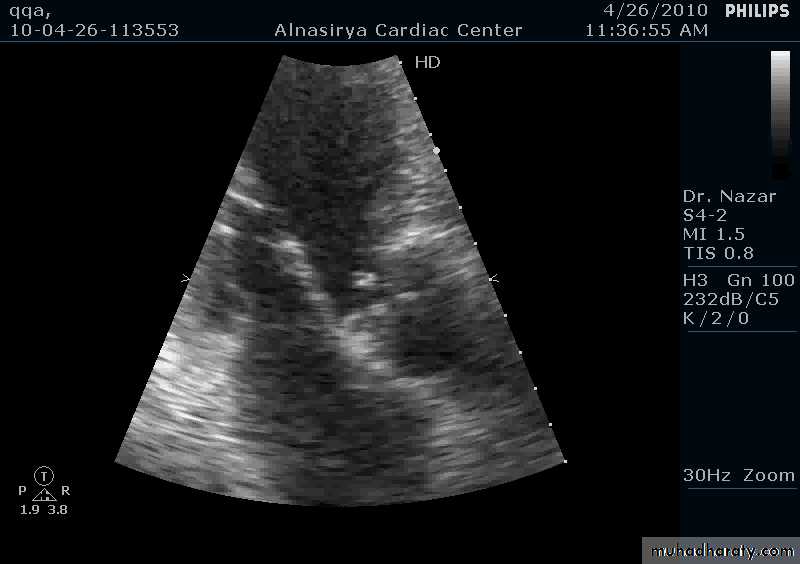

VEGETATIONS

36

37

38

39

40